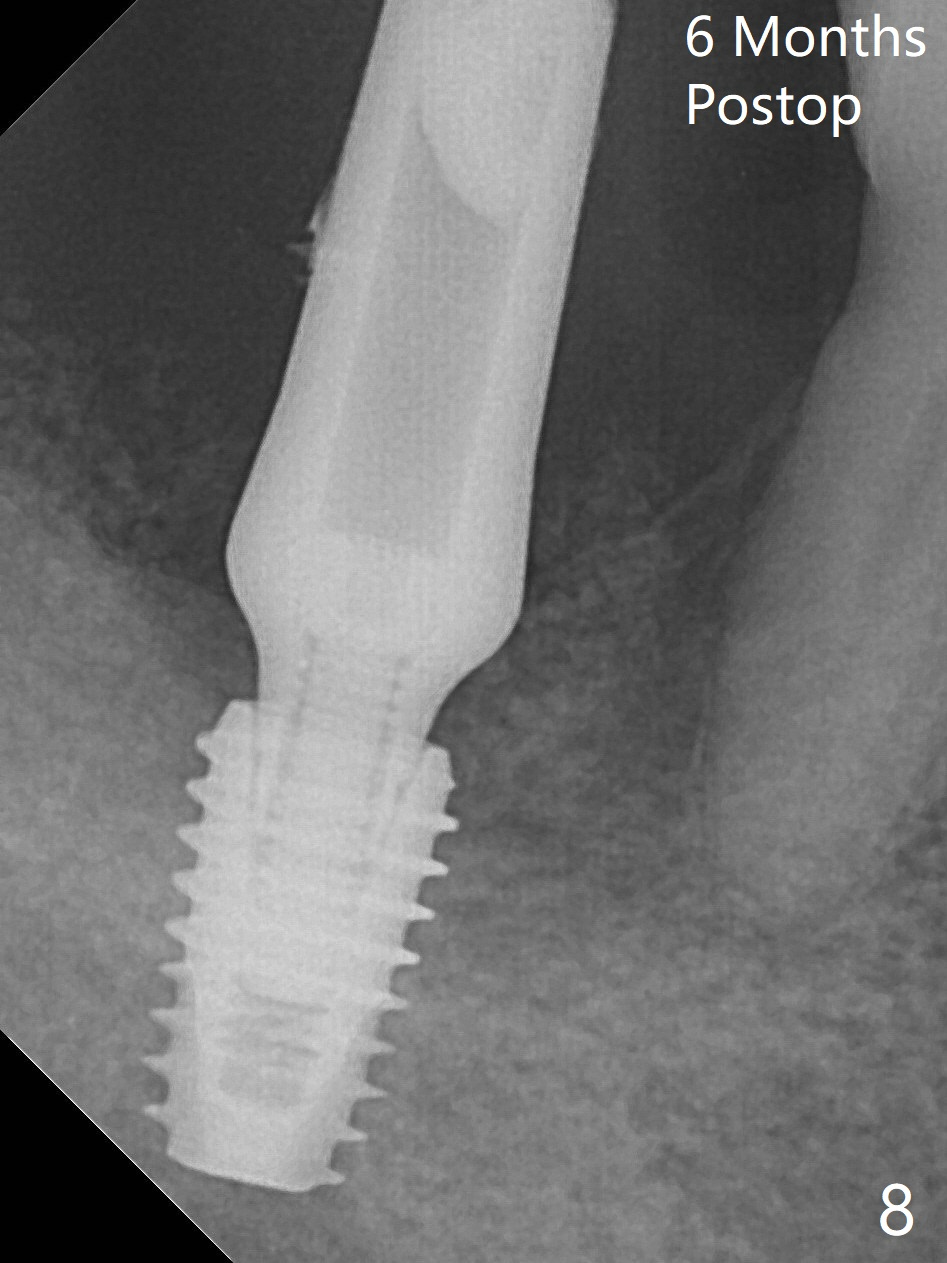

Due to limited bone height confirmed intraoperatively, a shorter UF implant is placed with insertion torque 30 Ncm (Fig.6).  After placing a 6.5x5(5) mm abutment, Vanilla Graft (*) and PRF membrane and collagen plug, an immediate provisional is fabricated to close the remaining socket.  The tooth #32 is kept initially to increase the stability of the provisional and removed 8 day postop because of discomfort.  A 5.5(2.5) mm mill abutment is placed 3 months postop.  The implant seems ready for impression 6 months postop (Fig.8).